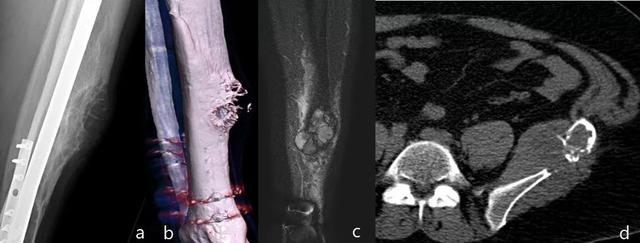

射线照相外观是一种局部性溶解病变,边界明确,具有皮质破坏,软组织肿块和无骨膜反应(图18)。

图18:15年前用固定治疗的胫骨干骨折,愈伤组织区的疼痛性溶解性病变(a和b)。病变是扩张的,皮质中断,伴有相关的软组织成分(c)。在扩展研究中,在左髂骨中观察到另一个具有相似特征的病变(d)。胫骨病变活检的结果是多灶性上皮样血管内皮瘤。